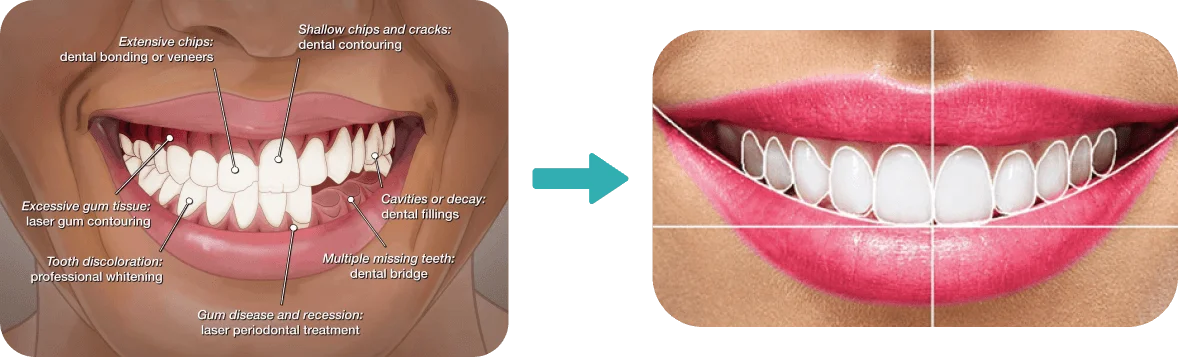

With our advanced smile makeover in Kochi, you can achieve a stunning transformation tailored specifically to your needs. From correcting misaligned teeth and closing gaps to whitening, reshaping, or enhancing your overall smile, our customized treatments are designed to bring out the best version of you.